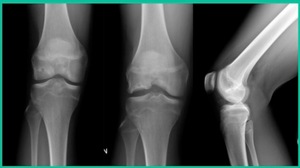

Now, we’ll shift to the adult. This is a 27-year-old. Right knee swelling, activity-related, and classic failed nonsurgical treatment on the lateral side of the knee.

This will probably be fixed. It’s a big piece and we’ll try to preserve it. The literature shows that preservation does pretty well. In this instance, there’s very little bone. It’s somewhat dystrophic, not very encouraging in my mind.

We removed it, and you say, “Well, this is terrible.” Lateral side, how is he going to do? Interestingly, the natural history does not suggest that that person will do badly. Probably the worst ones are going to be the ones who fall off to the side into the trochlea and lateral meniscus.